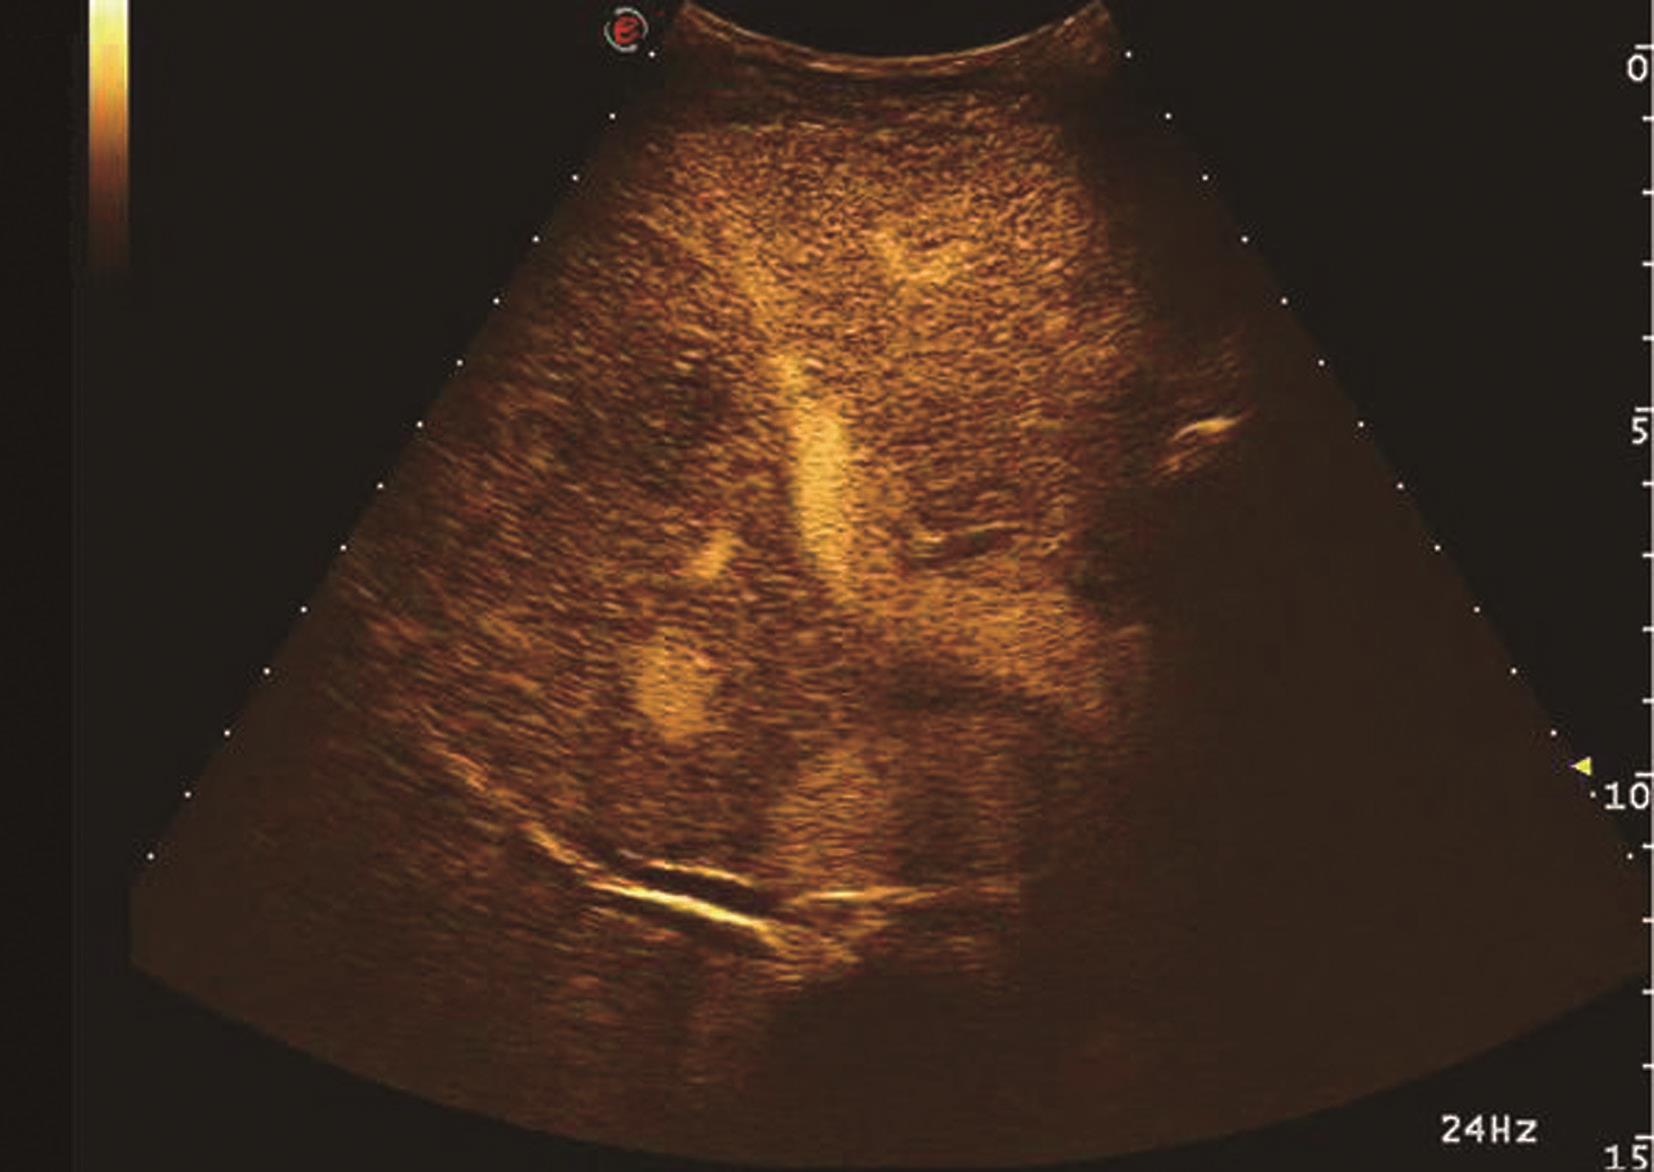

【声像图表现】

(1)肝细胞癌(hepatocellular carcinoma,HCC):

是肝脏最常见原发性恶性肿瘤,绝大部分病例与乙、丙型肝炎和肝硬化有关,占肝恶性肿瘤的80%~90%,男性多见,与乙肝和黄曲霉素相关,分为块状型、结节型、弥漫型及小癌型。在肝硬化的患者中,小的局灶性病变几乎代表着早期肝细胞癌或增生结节。小肝癌二维灰阶图像如图5-21-17所示。

图5-21-17 小肝癌二维灰阶图像

1)灰阶超声:

C.肿块内部回声类型:①低回声型:肿瘤回声低于周围肝组织。常呈圆形或类圆形,边界较清,具有细包膜,病变较小,常仅1~2cm,内部回声欠均匀,后方回声略增强。②高回声型:肿瘤回声高于周围肝组织,内部回声多不均匀。外形可为圆形或不规则分叶状,部分有假包膜形成者界限清晰。此型癌肿多较大。③等回声型:此型回声肝癌与周围肝组织密度相似,仅有微弱分界,易漏诊。对可疑病灶可使用高频超声进行检查,增加病灶检出率。④混合回声型:此型多见于体积较大的肝癌,癌肿内可同时出现多种类型回声,多种回声交织混合成为一体;如癌肿内出现不规则无回声区,其内可见点状或斑状高回声,多为癌肿内出血、坏死或液化。⑤弥漫型:癌肿数目众多,呈弥漫散布于整个或局部肝脏,直径多在1cm左右。内部回声高低不均匀。该类癌肿常伴有肝硬化,在声像图上有时很难与肝硬化结节鉴别,但弥漫型肝癌易伴发门静脉及肝静脉内癌栓和肝脏深部组织回声衰减。